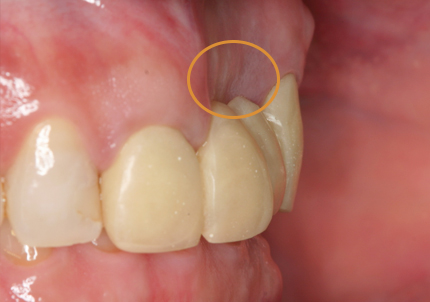

1.初診時口腔内写真(2018年10月)

➡審美領域における骨吸収を防ぐためのPET技法の歴史

近年、審美インプラント治療の進化により術者サイドの技術的、肉体的ストレスの軽減、患者サイドへの外科的侵襲度の劇的な軽減を可能とするテクニックが報告されている。審美領域で抜歯を行う際、束状骨の吸収により抜歯窩の形態を維持できず、唇・頬側の骨吸収が起こる。